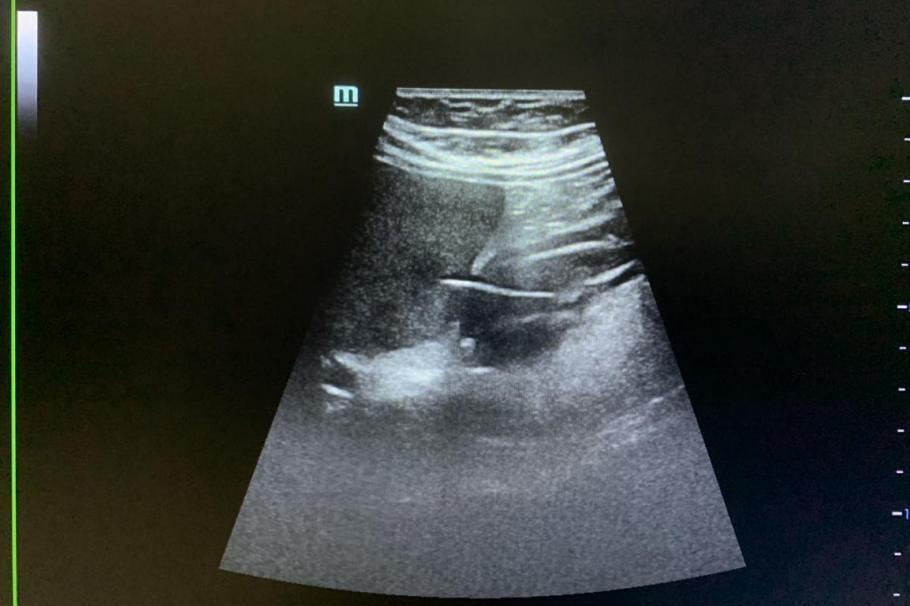

超声科

这里是清华长庚超声科

被诊断为可疑胃癌的患者

张华斌主任 谭庆亭医师反复检查

探头下的黑白世界里

“一根刺”终露真身

最终判定出竹签刺穿胃壁

进入肝脏的罕见病例

“我第一次,见到了送给自己的匾”

这是认真换来的价值

更换来了一个生命的新春